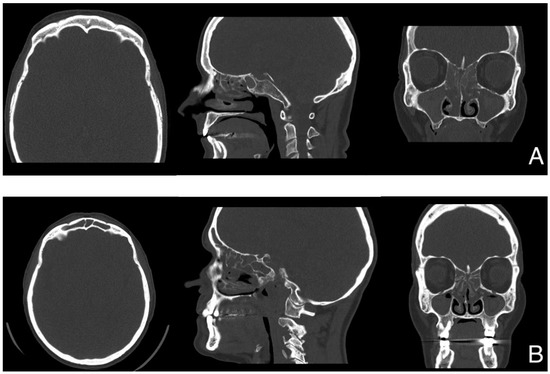

| Lund-Mackay score | 18/20 * | n.a. | 22/24 | n.a. |